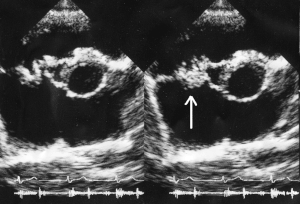

Vegetation on the tricuspid valve by echocardiography. Arrow denotes the vegetation.

In general, the Duke criteria should be fulfilled in order to establish the diagnosis of endocarditis.[5][31] Although the Duke criteria are widely used, they have significant limitations.[5] For example, the sensitivity of the Duke criteria for detecting infective endocarditis decreases when prosthetic heart valves are present.[5]

As the Duke criteria rely heavily on the results of echocardiography, research has addressed when to order an echocardiogram by using signs and symptoms to predict occult endocarditis among patients with intravenous drug abuse[32][33][34] and among non drug-abusing patients.[35][36] However, this research is over twenty years old and it is possible that changes in the epidemiology of endocarditis and bacteria such as staphylococci make the following estimates incorrect.